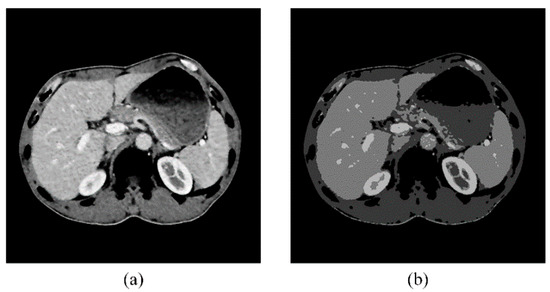

Kidney segmentation from abdominal computed tomography (CT) images is essential for computer-aided kidney diagnosis, pathology detection, and surgical planning. This paper introduces a kidney segmentation method for clinical contrast-enhanced CT images. First, it begins with shape-based preprocessing to remove the spine and ribs. [...] Read more.

Kidney segmentation from abdominal computed tomography (CT) images is essential for computer-aided kidney diagnosis, pathology detection, and surgical planning. This paper introduces a kidney segmentation method for clinical contrast-enhanced CT images. First, it begins with shape-based preprocessing to remove the spine and ribs. Second, a novel clustering algorithm and an initial kidney selection strategy are utilized to locate the initial slices and contours. Finally, an adaptive narrow-band approach based on active contours is developed, followed by a clustering postprocessing to address issues with concave parts. Experimental results demonstrate the high segmentation performance of the proposed method, achieving a Dice Similarity Coefficient of 97.4 ± 1.0% and an Average Symmetric Surface Distance of 0.5 ± 0.2 mm across twenty sequences. Notably, this method eliminates the need for manually setting initial contours and can handle intensity inhomogeneity and varying kidney shapes without extensive training or statistical modeling. Full article